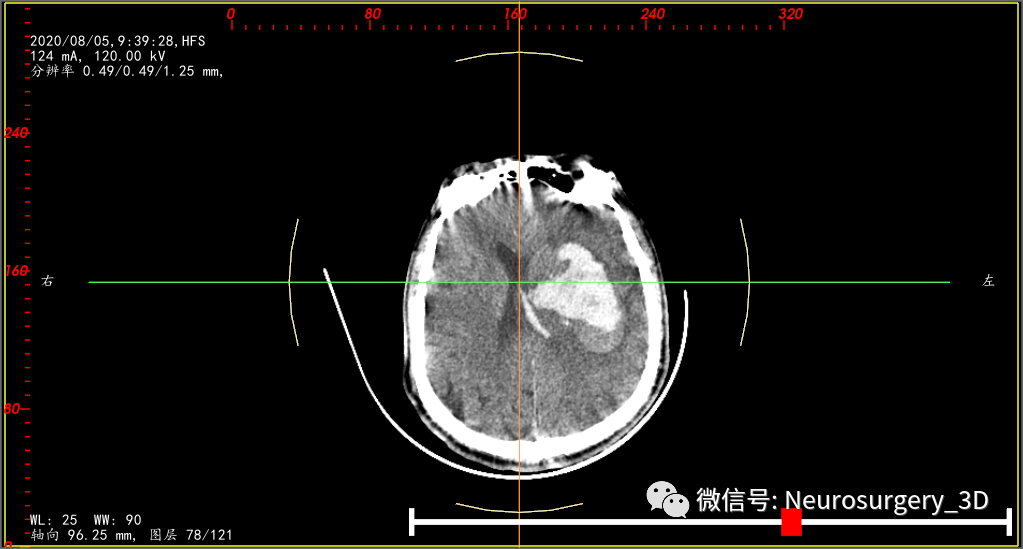

再来一例病例(2020年8月5日9:39)入院,王友某,男,61岁,入院时CT,也是高低密度分层,像不像活动性出血?

微创钻孔置管引流术后4小时CT复查(引流管位于血肿中心)